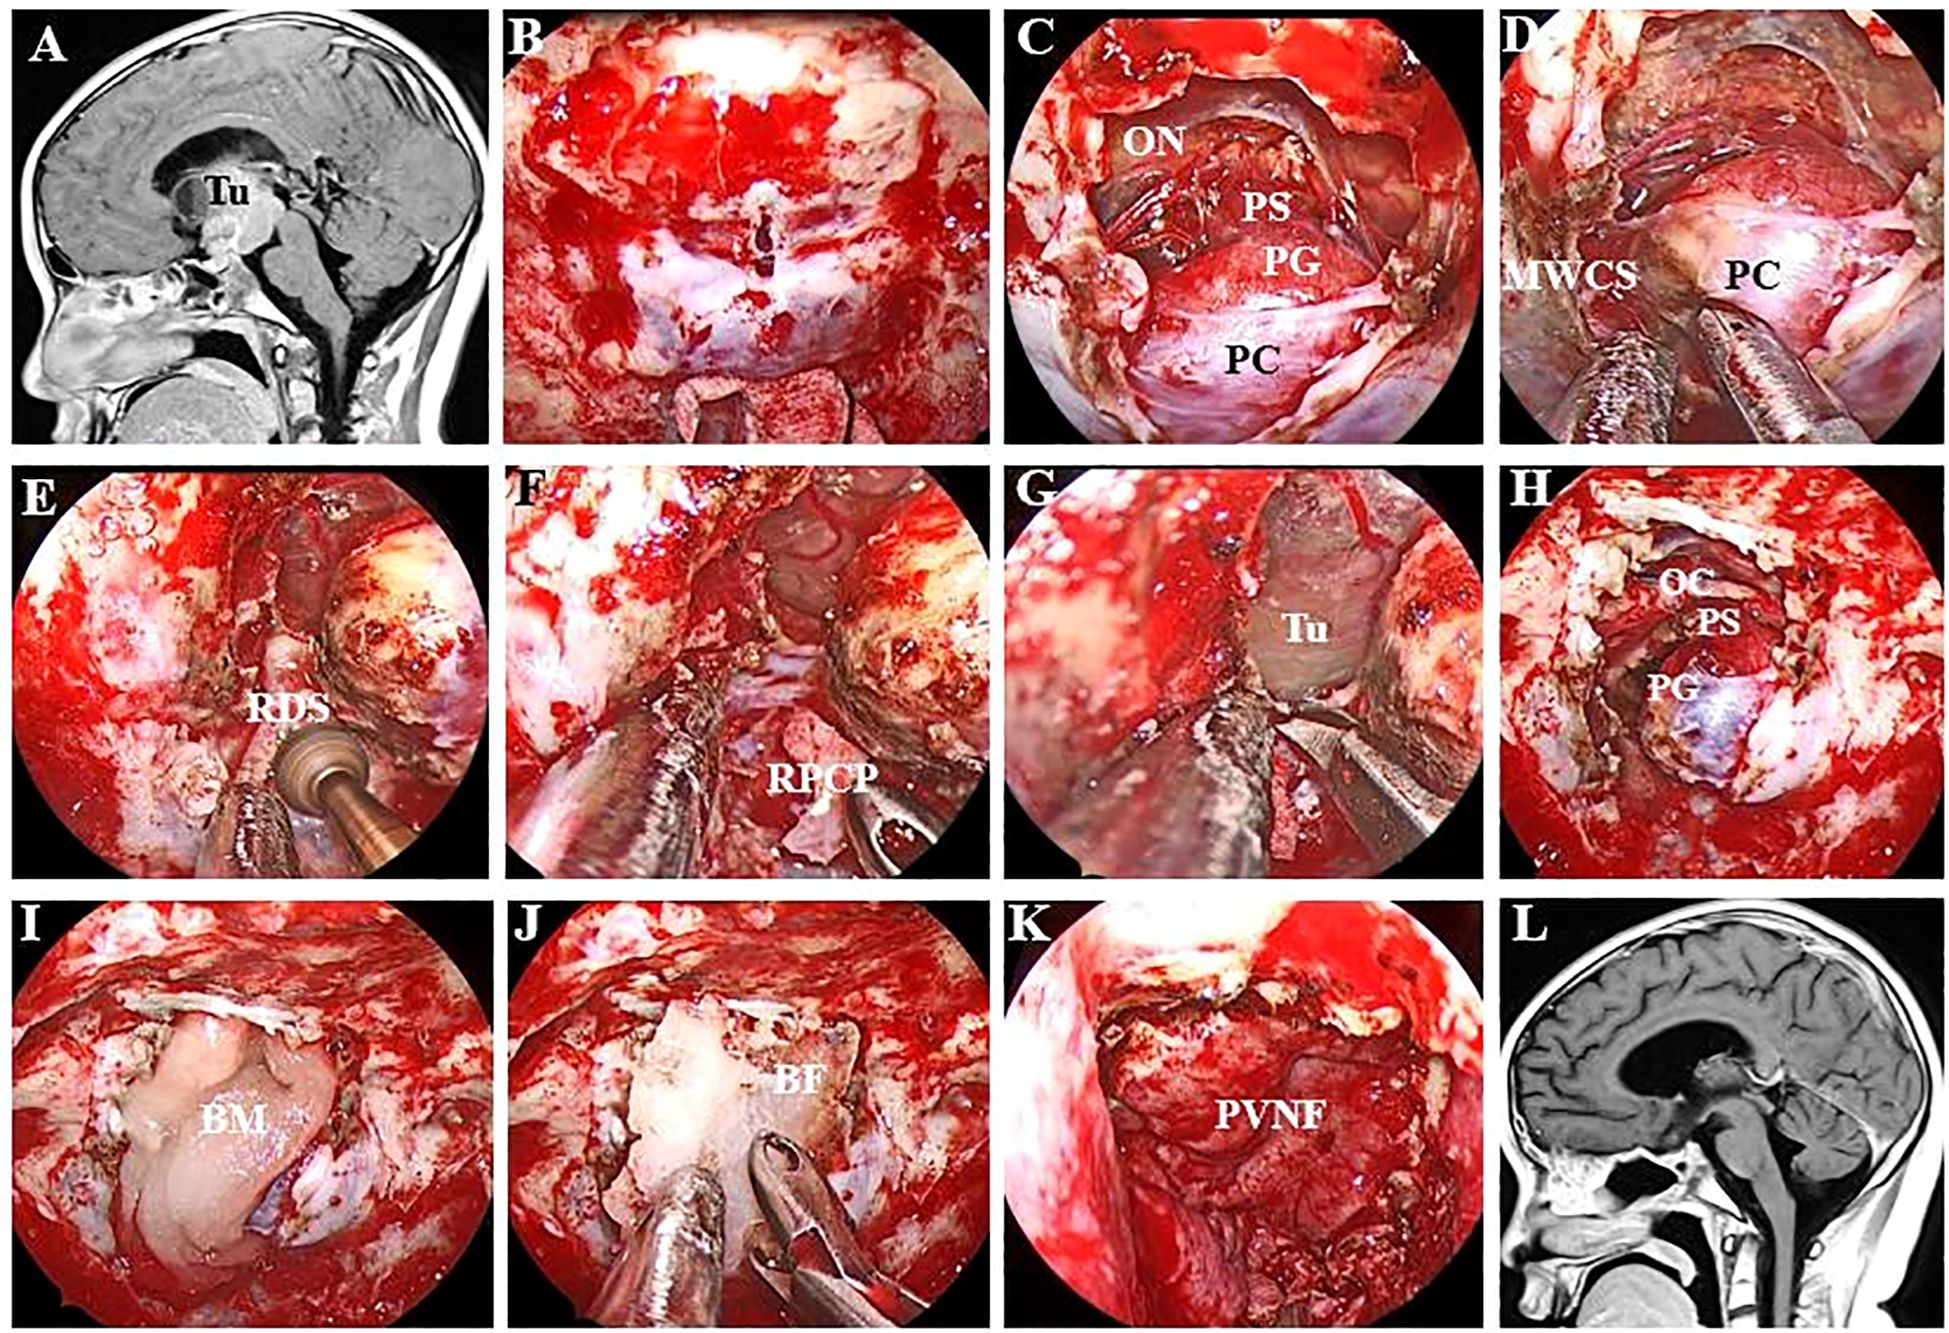

Opening the dura is the key to this procedure Figure 2. The authors favour intradural transposition, cutting the pituitary ligaments and IHA in the space of the MWCS and pituitary capsule, avoiding opening the CS laterally and violating the tight pituitary capsule medially. One-sided PGT (hemitransposition) was performed on the ipsilateral side of the tumour, and a contralateral approach was utilized only for the treatment of tumours located behind the dorsum sellae and ICAs.

Figure 2. Endoscopic endonasal view of the procedure and nuances of intradural PGT. (A) Preoperative MR image showing a large craniopharyngioma in the retroinfundibular area. (B) A longitudinal dural incision was made at the site of the sellar tubercle. (C) The dura mater was extended upwards and downwards without injuring the pituitary capsule. (D) The pituitary ligament between the MWCS and the pituitary capsule was excised, after which the PG was displaced laterally. (E) The DS was resected via high-speed drilling, and the clival dura was exposed. (F) The right PCS was removed to provide more space for manipulation inside the interpeduncular cistern. (G) The clival dura was cut downwards to expose the tumour more effectively. (H) The structure of the PG and optic chiasma was intact after complete tumour resection. (I) An absorbable artificial biomembrane was placed as the first step. (J) An in situ bone flap was placed on the biomembrane for complete osseous reconstruction. (K) A vascularized pedicled nasoseptal flap was used to repair the defect. (L) MRI revealed no residual tumour or recurrence. Tu, tumour; ON, optic nerve; PS, pituitary stalk; PG, pituitary gland; PC, pituitary capsule; MWCS, medial wall of the cavernous sinus; RDS, right dorsum sellae; RPCP, right posterior clinoid process; BM, biomembrane; BF, bone flap; PVNF, pedicled vascularized nasoseptal flap.

At the beginning of the procedure, the dura overlying the tuberculum was vertically incised, and then the superior intercavernous sinus was ligated and transected. The dural opening was subsequently extended superiorly and inferiorly to communicate with the suprasellar and sellar regions. After sharp dissection of the suprasellar arachnoid and early exposure of the PS, superior hypophyseal artery (SHA) and optic chiasma (OC), the dural opening is further extended laterally and inferiorly until the inferior intercavernous sinus is coagulated and cut to debond the anterior sellar dura bands early. These steps result in a wide intradural corridor to split the pituitary ligaments and cut off the ipsilateral IHA, after which the PG/PS can be displaced and rotated anteriorly and contralaterally without any dural attachment.